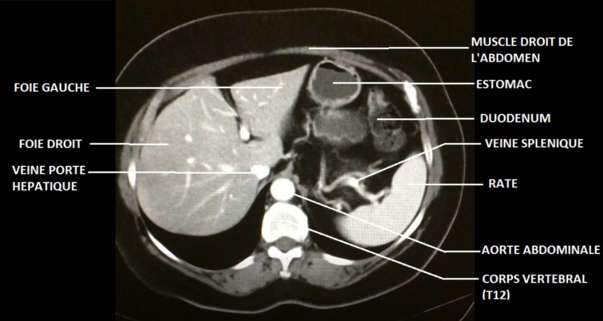

En bonus pour mieux visualiser, je te joins aussi une coupe axiale issue d'une tomographie sur laquelle tu visualises bien la

vertèbre qui se situe en arrière de l'aorte et la

peau (le liseré gris) qui entoure l'ensemble des éléments

Petit rappel : concernant l'orientation, on suit ici la

convention radiologique (l'orientation est la même que sur le schéma ci-dessus

)